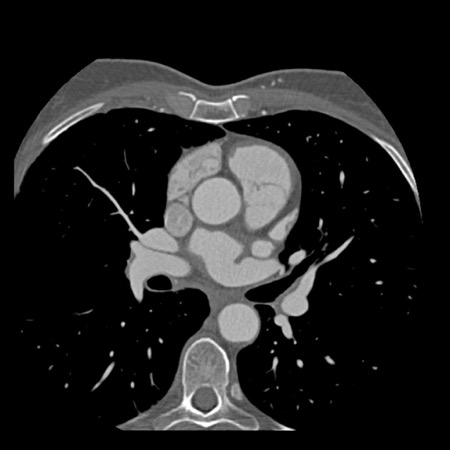

case 2 – CAD-RADS 5/P2/S

First, scroll through the CTA images.

How would you describe the findings on the coronary CTA?

The findings are:

- Stent in the mid

LAD with low-attenuation within the stent suggestive of minimal in-stent

restenosis (<25%). Non-calcified plaque distal to the stent

causing mild stenosis (25-49%). Notice bridging on a short segment in

the distal LAD. - Non-calcified

plaque in the LCX causing mild stenosis (25-49%). - Occlusion of the

proximal OM1 branch with distal filling. - Calcified and

non-calcified plaques in the proximal RCA causing mild (25-49%) stenosis. - Total plaque burden

is moderate based on SIS (four segments including proximal RCA, mid LAD, prox

LCX and OM1).

Due to the occlusion of OM1 branch and presence of the stent, this case

reads as CAD-RADS 5/P2/S, which means that this patient needs further

diagnostic workup.